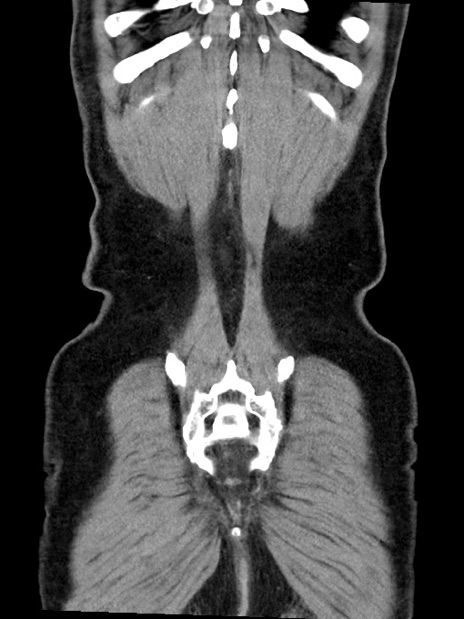

横断像

【症例】70歳代 男性

【主訴】腹部膨満、嘔吐

【現病歴】昨日より腹部膨満感出現。本日増悪し、仙痛出現。嘔吐あり、受診。

【既往歴】糖尿病、胆摘後

【身体所見】BP 149/80mmHg、HR 74/min、BT 35.9℃、腹部:膨満、軟、圧痛なし。腸雑音減弱あり。上腹部正中切開瘢痕あり。

【データ】WBC 13500、CRP 1.72